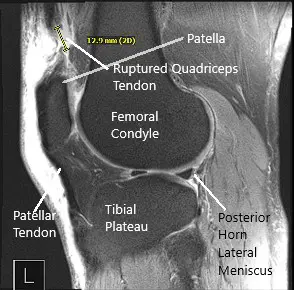

He was diagnosed with quadriceps rupture clinically. MRI of the right knee was performed and suggested a full-thickness rupture of the distal quadriceps tendon occurring 1.8 cm proximal to the patellar insertion site and resulting in a tear gap measuring up to 1.5 cm